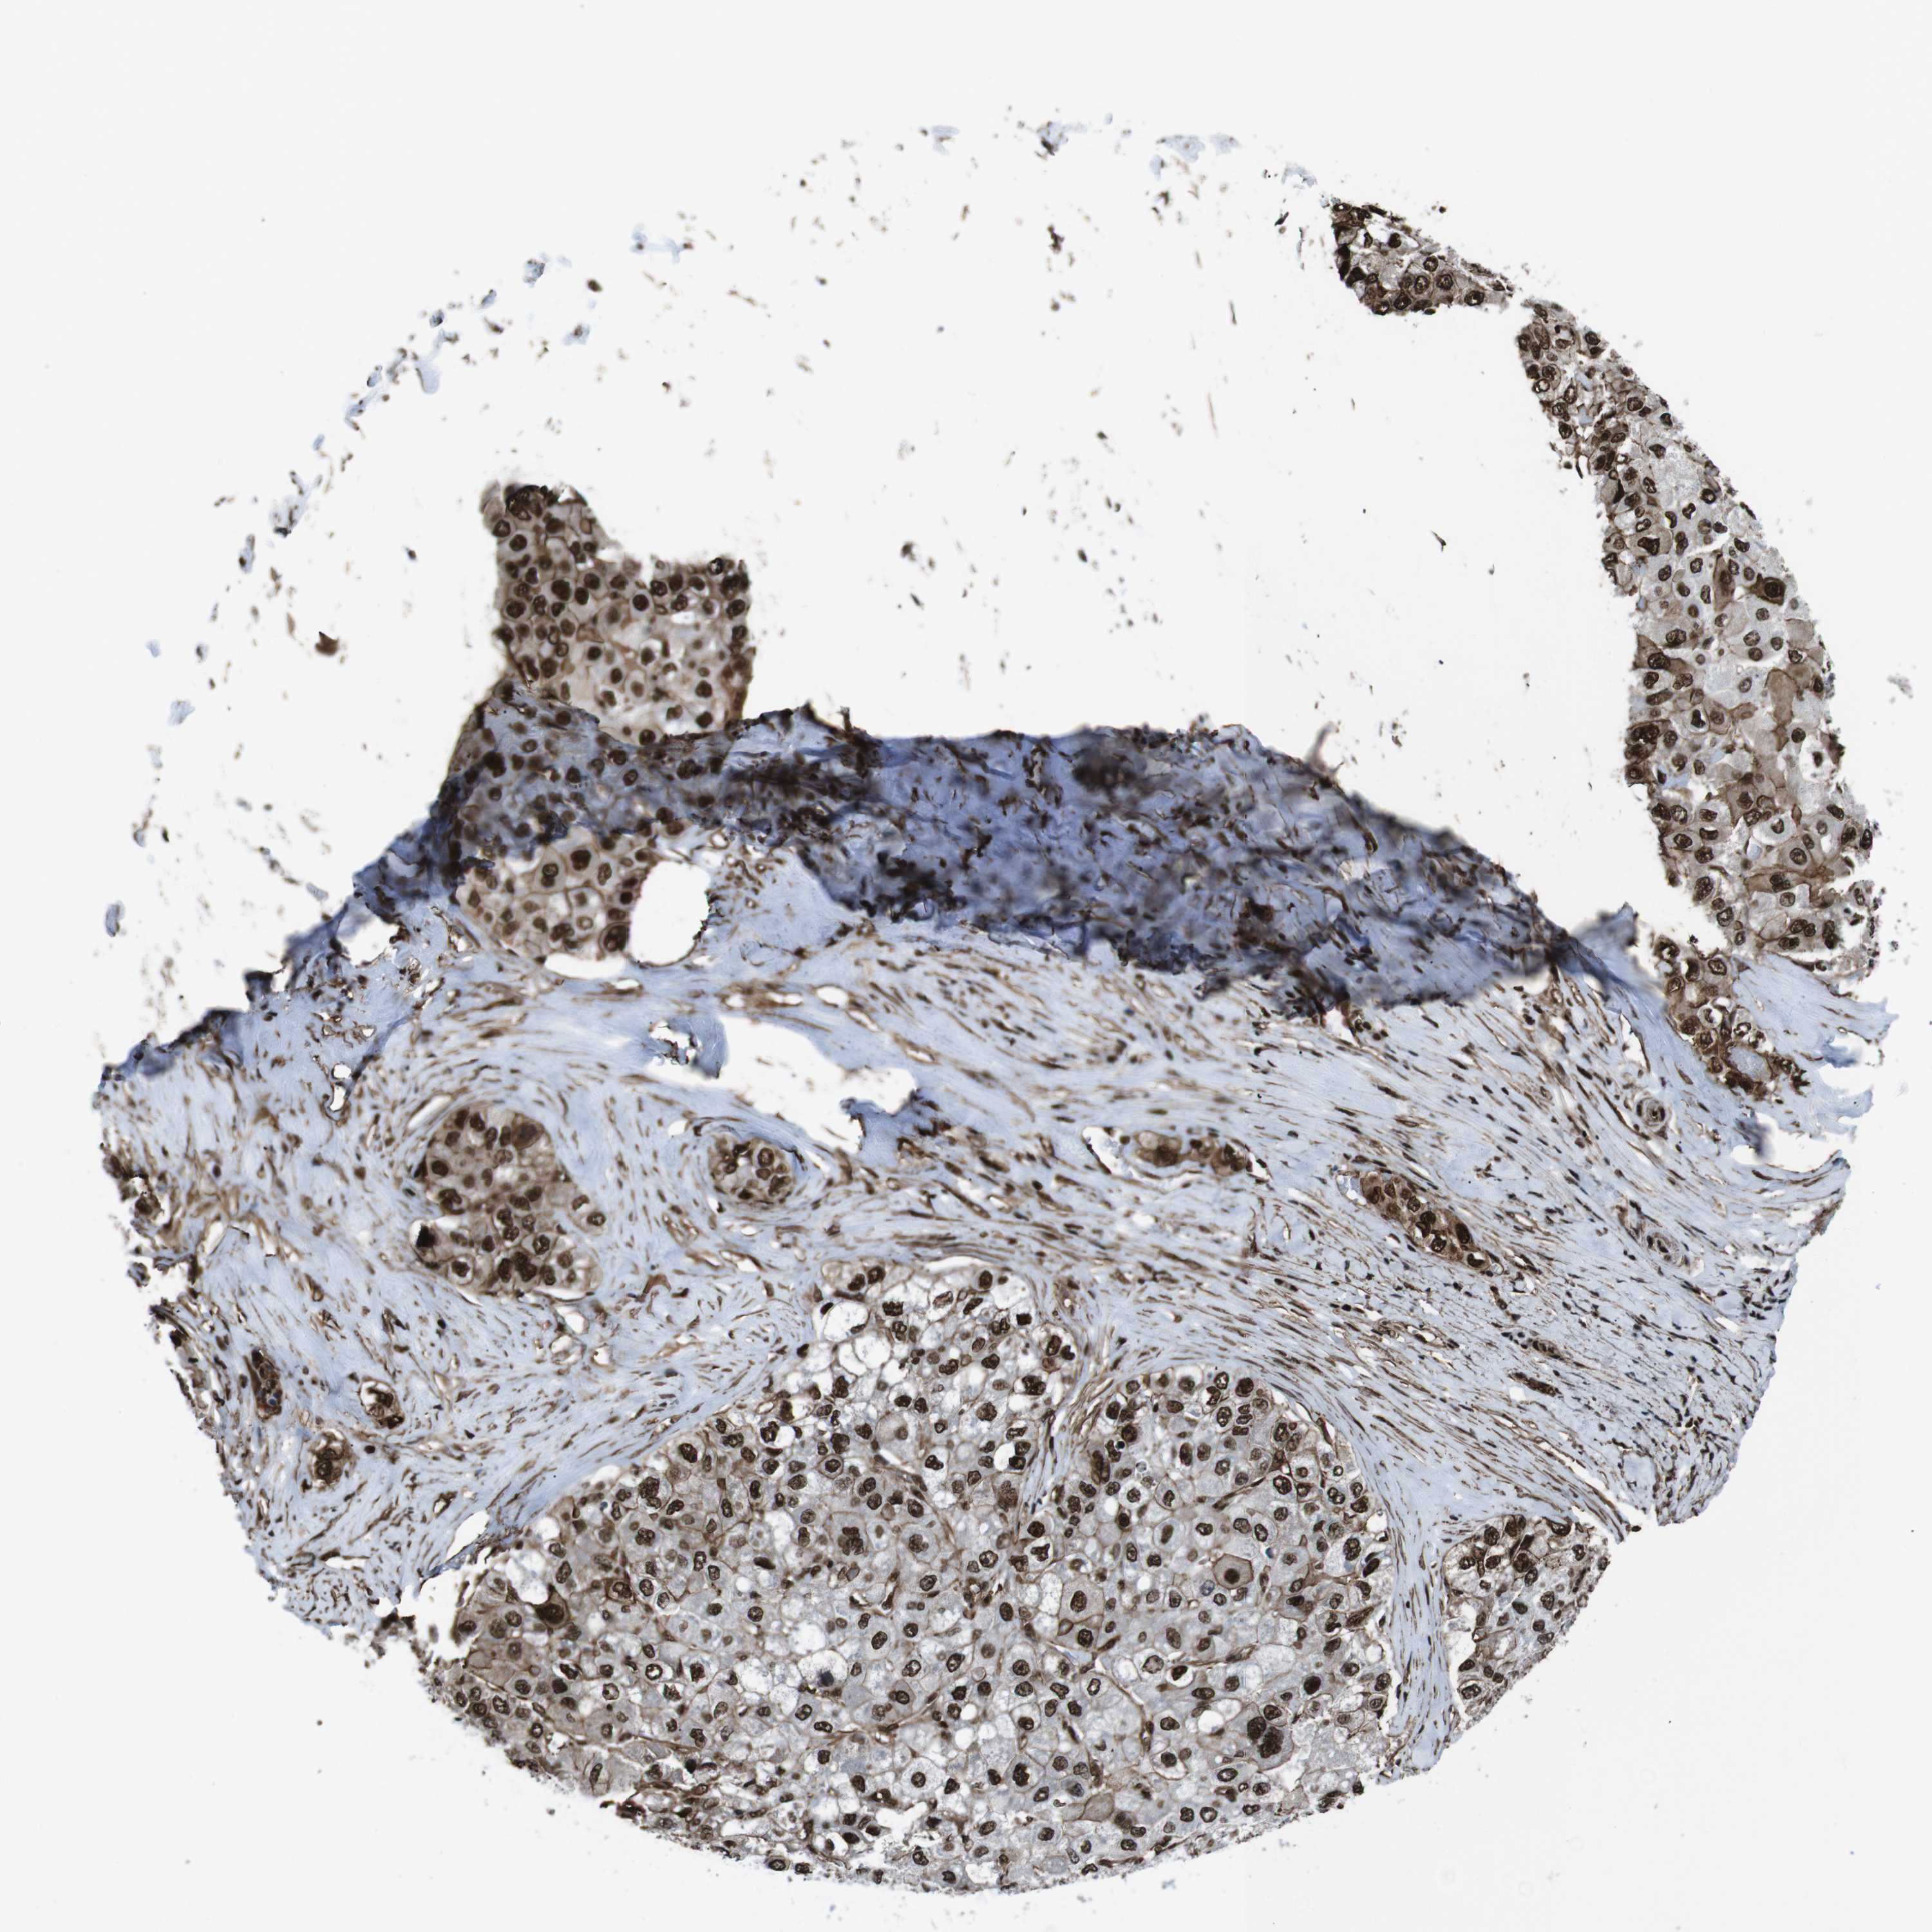

LIVER CANCER - Protein expressioni

A mouse-over function shows sample information and annotation data. Click on an image to view it in a full screen mode. Samples can be filtered based on level of antibody staining by selecting one or several of the following categories: high, medium, low and not detected. The assay and annotation is described here.

Note that samples used for immunohistochemistry by the Human Protein Atlas do not correspond to samples in the TCGA dataset.

Antibody stainingi

Antibody staining in the annotated cell types in the current human tissue is reported as not detected, low, medium, or high, based on conventional immunohistochemistry profiling in selected tissues. This score is based on the combination of the staining intensity and fraction of stained cells.

Each image is clickable and will lead to virtual microscopy that enables deeper exploration of all samples and also displays staining intensity scores, fraction scores and subcellular localization as well as patient and tissue information for each sample.

Antibody HPA041057

Antibody HPA058707

Antibody CAB011532

Staining

High

Medium

Low

Not detected

Intensity

Strong

Moderate

Weak

Negative

Quantity

>75%

75%-25%

<25%

None

Location

Nuclear

Cytoplasmic/membranous

Cytoplasmic/membranous,nuclear

Cholangiocarcinoma

Carcinoma, Hepatocellular, NOS